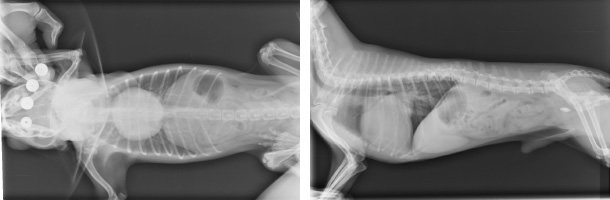

血管の太さや、肺水腫の有無と言った肺の状況を確認することで適切な治療につなげることができます。

レントゲン検査

猫は心筋症関連の心疾患が多く、聴診器では異常が見つからないこともあるため、

早期に診断をつけるためにはレントゲンや心臓病超音波検査などでの

精密な検査を行うことが大切になります。